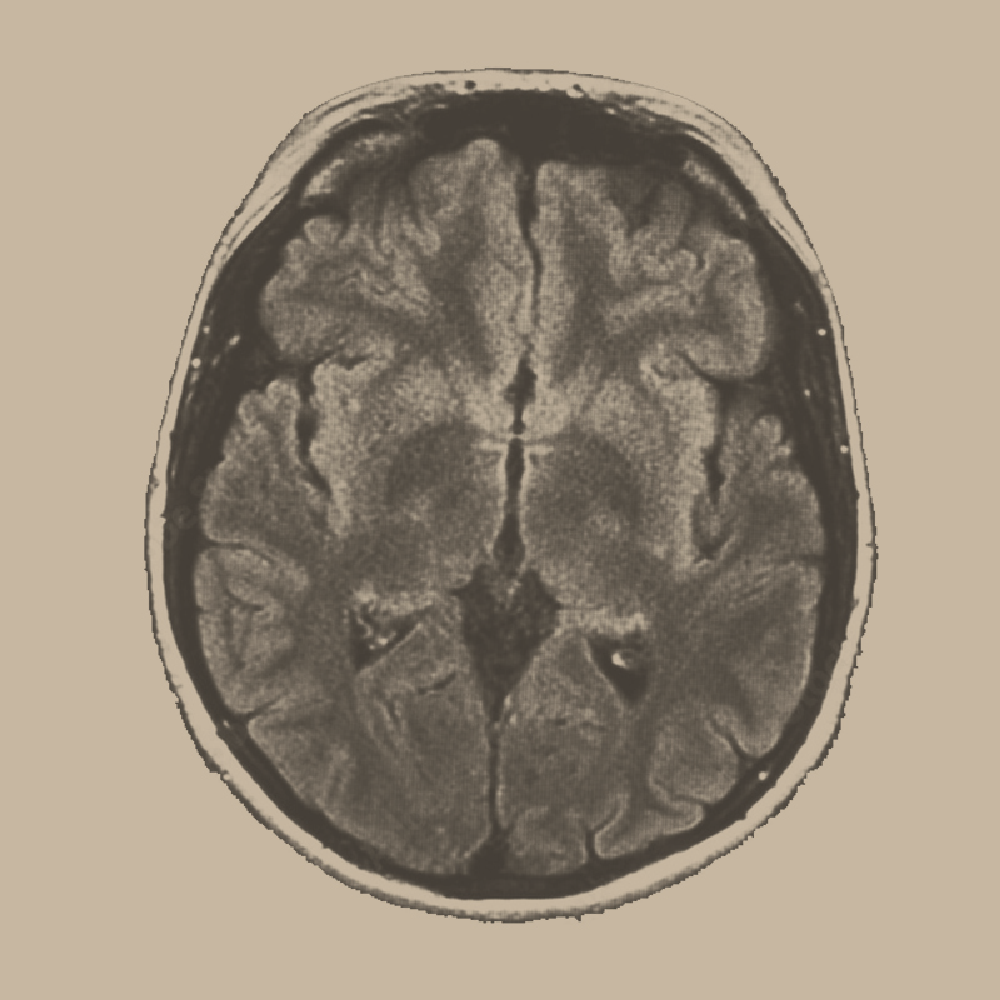

Functional Fragrance can interact with the brain, not just delight the senses. When you inhale scent, aromatic molecules bind to olfactory receptors in the nose, activating the olfactory bulb, the first neural structure to receive smell input, which uniquely bypasses the brain’s sensory relay station, the thalamus. This gives olfaction one of the fastest and most direct sensory routes into circuits that govern emotion, stress, memory and autonomic state.

Olfactory signals project into the amygdala (emotional salience, threat detection, anxiety and stress signalling), hippocampus (context and emotional memory), hypothalamus (circadian rhythm, hormones, sleep-wake timing and autonomic nervous-system regulation), orbitofrontal cortex (reward, emotional evaluation, wellbeing perception and choice), and the insula (internal body-state awareness, emotional processing and autonomic regulation). These regions are core to the lived experience of feeling alert, safe, calm, connected, or mentally clear. Key regions influenced by olfactory cues also include the amygdala, hippocampus, hypothalamus and orbitofrontal cortex - areas involved in emotion, stress response, circadian rhythm, memory and cognitive regulation.